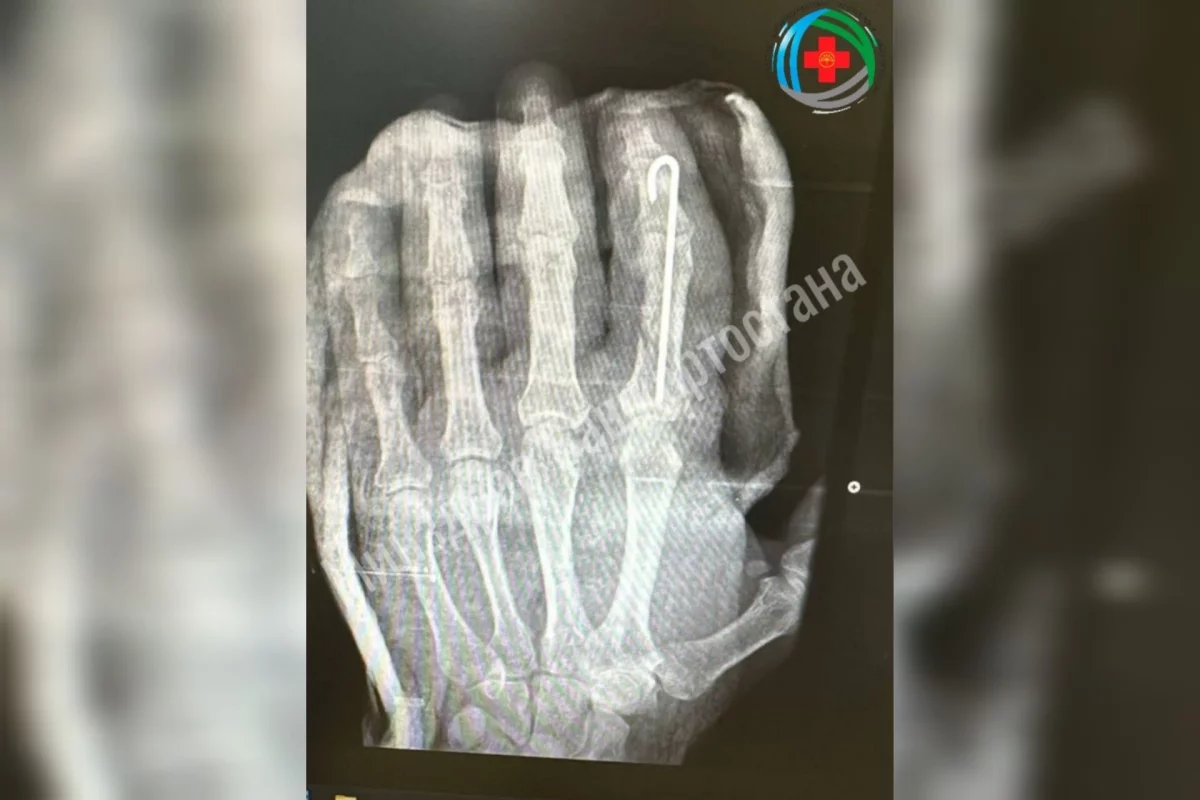

Медики приняли решение экстренно оперировать. Они провели ювелирную работу: восстановили мельчайшие сосуды, чтобы для возобновить кровоток, точно зафиксировали кости и реконструировали мягкие ткани для возобновления подвижности пальца.

«Палец прижился, и пациент уже делает первые успехи в движении. Сейчас он проходит восстановительное лечение, которое включает медикаментозную терапию, физиотерапию и лечебную физкультуру. По результатам лечения ожидается полное восстановление функций после завершения реабилитации», — прокомментировали в ведомстве.